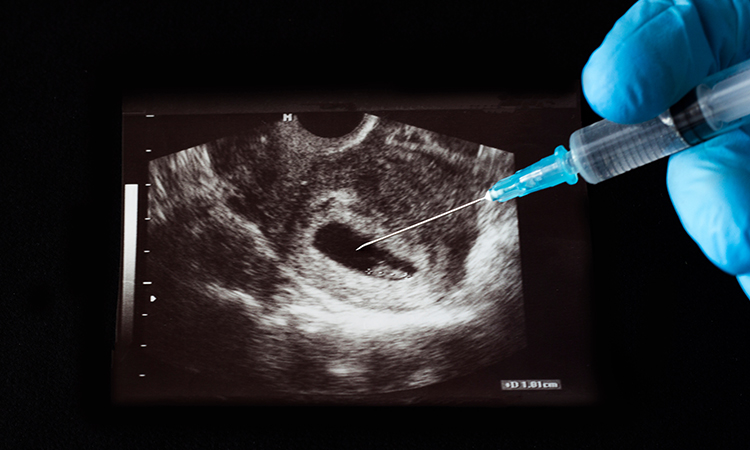

La defensa de los derechos humanos inicia con defender cualquier vida: abortar es matar. Porque defensores de la vida ante los homicidios hay muchos, pero en general evaden el caso del aborto.

¿De qué se trata? De la presión antivida para dar absoluta impunidad a quienes asesinen a una persona nonata. Del aborto, pues, término escondido tras la expresión más cómoda de “interrupción (legal) del embarazo”. Este lenguaje logra convencer a muchos de que se trata de ayudar a una mujer en problemas, lo de como dicen en broma “estar ligeramente embarazada”. Pero es algo que no es ninguna broma, se trata del peor crimen que la sociedad puede avalar, permitir, licenciar, liberar de responsabilidades, darle impunidad legal.

Pero mientras se utilice lenguaje que oculta lo que realmente es, muchas personas pensarán que está bien eso de permitir a las mujeres, impunemente, deshacerse de su hijo nonato, por medio del aborto. Y este término, aborto, también es fácil, desgraciadamente, de aceptar sin condiciones, pues permite a las mujeres, como se busca justificarlo, a vivir su vida sin el problema de cargar con un hijo no deseado (provenga de sexo impuesto o deseado).

Lo que insisto es que el lenguaje permite a los promotores del aborto, convencer a otras personas de que es razonable el despenalizar este delito. Aunque insistan en que realmente es delito, pero que no sea punible, bajo diversas condiciones, como el no haber cumplido cierto número de semanas de embarazo, y aun llegando al terrible grado de que se valga abortar un bebé al término del mismo, justo al dar a luz. Lo más grave es que se defienda la idea de despenalizar el dar muerte a un bebé inmediatamente después del parto. Y esto ya es algo que ni siquiera pueden llamar aborto.

Y abortar es, sin forma de evadirlo, matar una persona nonata (quienes todavía dicen que no es persona, sino una bola de células o algo así tienen la batalla perdida ante la ciencia médica). Y si en vez de hablar de aborto (y menos aún de “interrupción del embarazo”), se usa el lenguaje exacto, que es matar personas nonatas, es más fácil recurrir a la legítima defensa de los derechos humanos, en especial al derecho humano primigenio, el de la vida, sea de nonatos o nacidos.

Si alegamos que la defensa de los derechos humanos inicia con defender cualquier vida, vamos directo al grano: abortar es matar. Porque defensores de la vida ante los homicidios hay muchos, pero en general evaden el caso del aborto.

Quienes alegan que ante un preocupante aumento de asesinatos de mujeres (por ser mujeres) que se debe defender la vida, con la frase conocida de “ni una más”, o la otra de “ni una menos” (viva), deben enfrentar el hecho de que, de cada 100 bebés asesinados en el vientre materno, 49 son mujeres. Y peor aún cuando el aborto “selectivo” se realiza porque el bebé es mujer, se le está matando precisamente por ser mujeres: feminicidios, pues.

Ante las preocupaciones públicas por la inseguridad reinante, que permite que se asesinen personas impunemente, en especial mujeres y menores de edad (allí sí van los varoncitos), se debe incluir la defensa de las personas nonatas, que no se cometan crímenes en su contra impunemente, al incluir en legislaciones penales, que el delito de llámenle aborto, interrupción del embarazo o algo semejante, la liberación de responsabilidad penal. Si se lucha contra la impunidad, tenemos el derecho a exigir que el crimen de matar nonatos no puede gozar de impunidad.